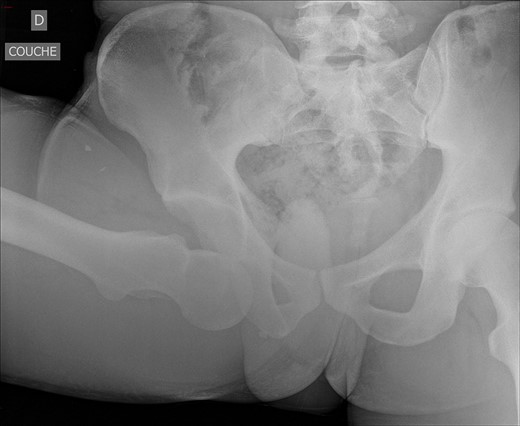

An antero-posterior pelvis radiograph was obtained and showed inferior dislocation of the right femoral head with no associated fracture (Fig. 1). Closed reduction was successfully achieved under general anaesthesia. Reduction consisted of:

After reduction, the neurovascular examination remained normal. Pelvis CT-scan was performed and showed a bifocal fracture of the hip associating a non-displaced inter-trochanteric fracture and a non-displaced capital fracture (Fig. 2). Patient was discharged on day 5 with strict bed rest for 6 weeks.